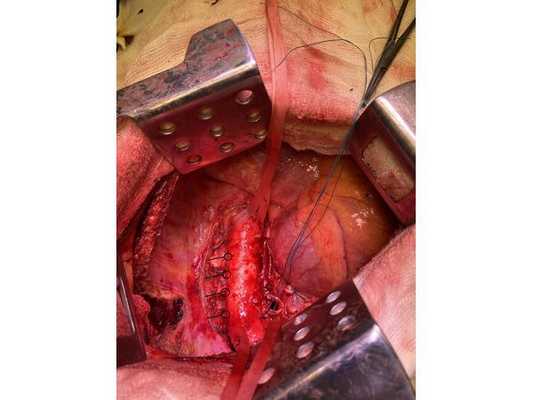

Интраоперационное фото: клипированные межрёберные артерии; аорта на тесёмочных держалках по краям зоны резекции адвентиции; культя главного бронха с провизорными швами при ушивании по Оверхольту

4. Острым путём отсечён левый главный бронх, при этом обнаружено, что опухоль распространяется перибронхиально. Культя левого главного бронха реампутирована (ампутирована повторно) в пределах визуально здоровой ткани стенки бронха, до 1,5-2 см от карины трахеи (гребня хряща между разделением двух главных бронхов). Центральная часть культи левого главного бронха ушита по Оверхольту.

5. Отступив по грудной стенке от края врастания опухоли в аорты на 2 см, рассечена и отсепарована (отделена хирургически) париетальная плевра и адвентиция аорты. Аорта мобилизована по типу "ручки чемодана" и взята на тесёмочные держалки выше и ниже места врастания опухоли.

6. Скелетизируя грудную стенку и аорту, с перевязкой левых межрёберных артерий, на участке рёбер 4, 5, 6 и 7 выполнена полуциркулярная резекция адвентиции аорты, мягких тканей грудной стенки с париетальной плеврой и тканей средостения.

7. Пневмонэктомия. Проверка аэростаза (герметичности) под уровнем жидкости — просачивания воздуха в области культи бронха нет.